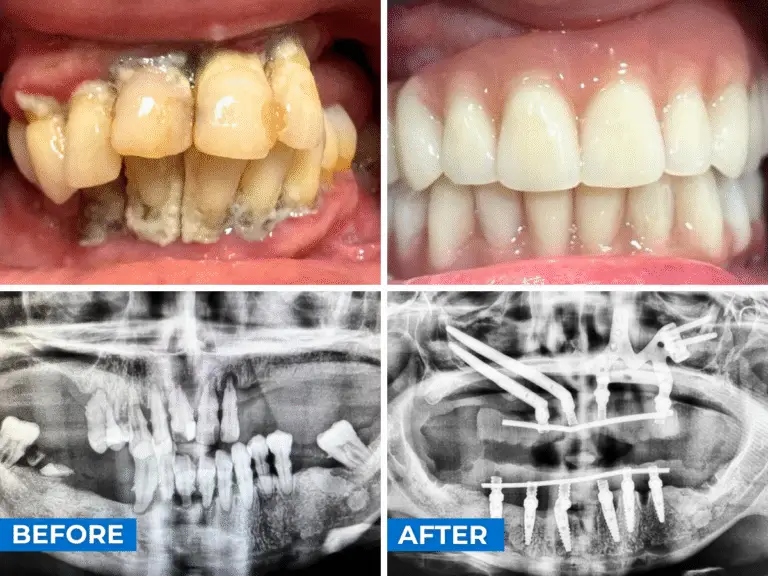

Patientenfall Beispiel A

Ein 38-jähriger Patient, der sich mit allgemeinem Knochenschwund, erheblicher Beweglichkeit und Infektionen vorstellt. Nach der CT-Untersuchung stellten sie fest, dass die Knochendicke sehr gering ist, und außerdem ist der Knochen im Bereich des Jochbeins extrem knapp und sehr dünn. Daher wurde beschlossen, im Oberkiefer individuell angepasste Implantate zu setzen, um den geringen verbleibenden Knochen zu nutzen, und im Unterkiefer eine Rehabilitation mit konventionellen Implantaten – sechs Implantaten – durchzuführen, die eine Sofortbelastung sowohl im Ober- als auch im Unterkiefer ermöglichen.

Auf dem Foto sehen Sie das Vorher und Nachher mit den provisorischen Prothesen unter Sofortbelastung.